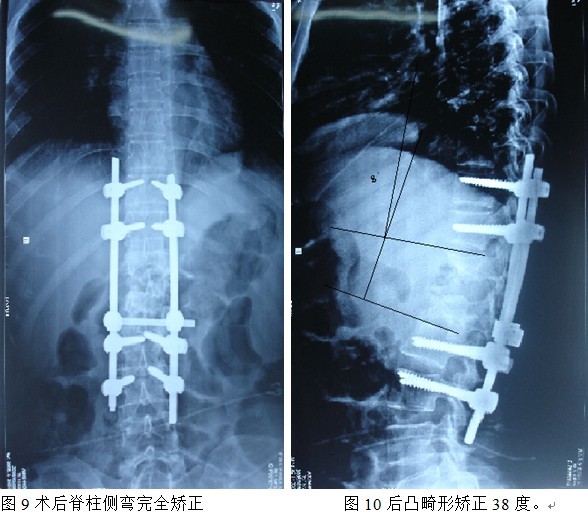

本组手术用时间3~4h , 平均3.5h 。术中出血300~500ml , 平均约350ml 。术后症状完全缓解,无神经功能障碍加重等并发症,1例营养差的老年患者伤口出现窦道,1例因肝功能差,术后未口服抗痨药,伤口出现窦道,经换药后二期愈合,其余病例伤口均一期愈合。马尾神经受损的患者术后基本恢复正常。术后一周后凸角平均 5.4°后凸畸形平均矫正90%以上, 最终后凸角平均8.3°,后凸角度平均丢失4.2°。随访3个月有87%(40/46)有骨痂形成,6个月91.3%(42/46)明显骨性愈合(见图),其余4例9-12个月内愈合,随访时间3-32个月,平均11个月,46例患者中2例在术后2个月和3个月时背部形成脓肿,换药后治愈。2例出院1月后并发结核性脑膜炎,治疗后好转。1例因椎弓根钉偏外,刺激神经根,5个月后从侧方脱出,疼痛加重,因前后路植骨完全愈合,取出后症状完全缓解。

中国学者金大地[22]等采用一期前路病灶清除植骨前路钢板固定治疗腰椎结核,平均18°的后凸畸形得以矫正,Mukhtar[23] AM等采用前路病灶清除植骨分期或同期后路固定治疗腰椎结核22例,术后后凸畸形矫正度数平均为27°。从我们的随访结果看,术后后凸畸形平均矫正度数为26.9°,后凸畸形平均矫正90%以上, 6个月-49个月后随访,后凸角度平均丢失4.2°。本术式也适用于结核所引起的弹性差的后凸畸形,对于病灶纤维化或骨化的非弹性后凸畸形,后路固定后,先行前路病灶、纤维化或骨化切除、松解,逐步刮除病灶、逐步撑开,达到畸形矫正和植骨的目的。